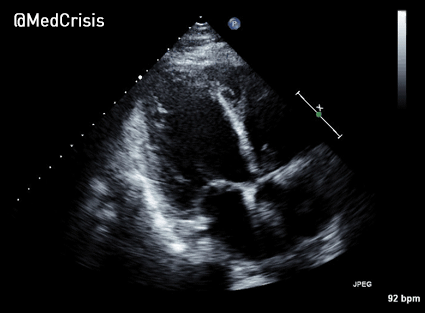

A bedside echocardiogram was performed.

A parasternal long axis view reveals the posterior mitral valve leaflet is tethered. The basal posterolateral wall is hypokinetic.

This parasternal short axis view gives the clearest demonstration of the problem. A regional wall motion abnormality is clearly seen affected the infero-septum and inferior wall. The rest of the left ventricle is contracting well.